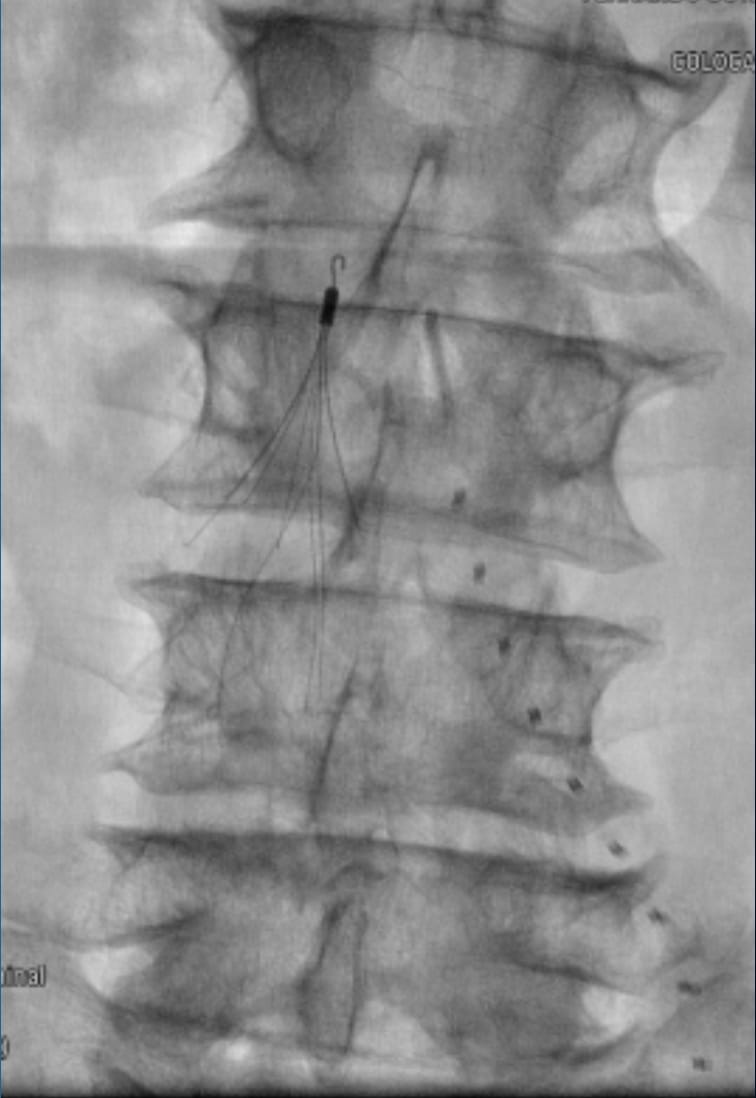

A patient with IVC atresia rolled into my office in a wheelchair. No options were offered for years. Successful IVC reconstruction. One week later, walked into my office for followup! One month later, living his best life, no pain and no limitations. #chogazi #irad #vascular #cardiotwitter @SIRRFS @SIR_ECS @SIRspecialists @VascularSVS @farkomd @AmputationSuck @ChengaziMD